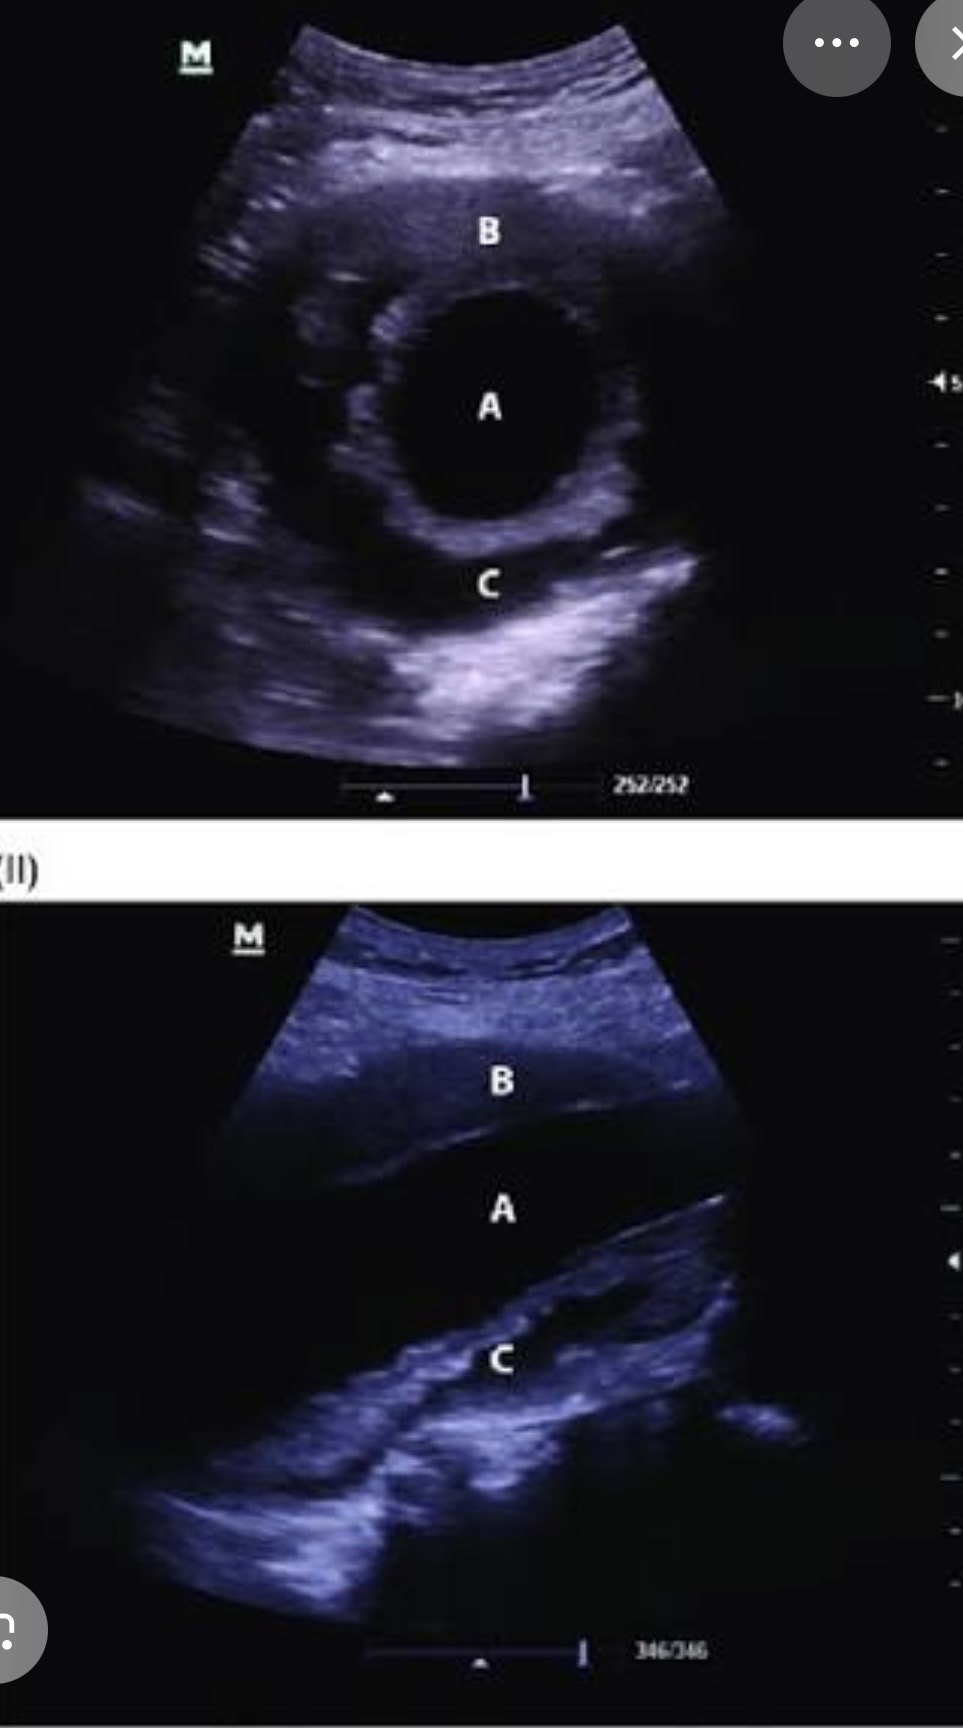

What plane is this

Transverse right lobe of liver

What plane is this?

Sagittal or long